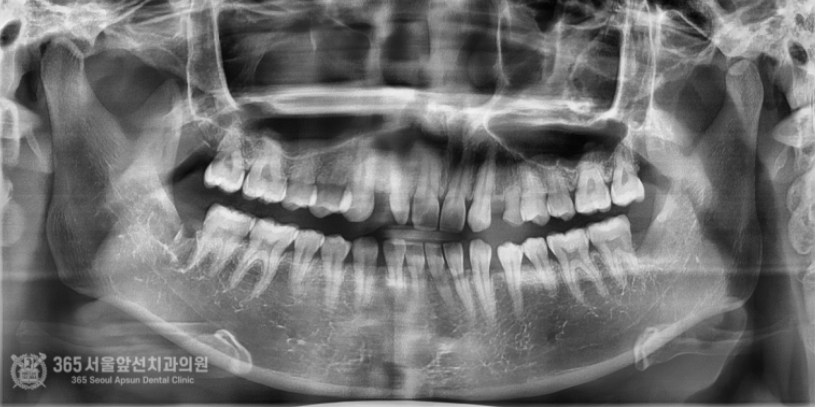

안녕하세요. 주안동치과 365서울앞선치과의원입니다. 하루에도 몇 건씩 사랑니가 불편하셔서 오시는 환자분들을 만나뵙고 있습니다. 환자분들께 치과에 대한 안좋은 기억을 여쭤보면 항상 빠지지않고 나오는 이야기가 바로 사랑니 발치인데요~ 그만큼 많은 환자분들께서 사랑니로 인해 불편감을 호소하고 계시고 발치도 많이 하고 가십니다. 하루에도 몇 건씩 발치를 하다보니 밥먹듯이 하는 진료가 되어버렸네요 ㅎㅎ 촬영일시 : 2024.06.25. 내원 당시 파노라마 엑스레이 사진 입니다. 간단한 사랑니 발치부터 완전 매복 사랑니까지 매일매일 다양한 사랑니 환자분들께서 찾아오십니다. 최근에 오셨던 환자분인신데요. 위와 아래 사랑니가 모두 매복된 형태를 보이고 있습니다. 매일매일 완전매복 사랑니 발치를 시행하고 있기에 매복 사랑니는 대수로운 문제가 아니지만 해당 환자분께서는 조금 특이한 양상이 있어서 포스팅을 하게 되었습니다. 사진 상 빨간색 동그라미 친 아래부분 사랑니의 경우 사랑니의 머리가 설측(혀쪽)으로 향하고 있는데요. 사랑니를 발치할때 기구 접근이 사랑니의 머리쪽으로 이루어져야 하므로, 사랑니 머리가 협측(볼쪽)으로 나와있는 것이 발치에 유리합니다. 즉, 해당 환자분은 사랑니발치 난이도가 꽤 높은 편 에 해당하는 특이한 형태였습니다. 촬영일시 : 2024.06.25. 내원 당시 CT 사진 : 아래쪽 사랑니가 뼈에 거의 묻혀있고 사랑니의 머리가 혀쪽으로 기울어져있는 것이 보입니다. 쉽지 않아보이네요. 촬영일시 : 2024.06.25. 여러 각도에서 CT 분석을 시행합니다. 비록 난이도가 높은 사랑니 발치에 해당했으나, 위아래 사랑니 모두 발치하는 것부터 봉합하는데 걸린 시간까지 총 12분이 걸렸고 환자분께서는 빠르고 정확한 발치에 만족하시며 귀가하셨습니다 ^^ (지혈 거즈를 물고 계셔서 비록 말씀은 못하셨으나 왼쪽 손으로 엄지척 해주셔서 뿌듯했습니다 ㅎㅎ) 촬영일시 : 2024.06.25. 안전하게 발치가 완료된 파노라마 엑스레이 사진입니다. 매일 사랑니 발치와 관련하여 다양한 환자분들을 만나뵙고 있는데요. 환자분들의 고통을 해결해드리고, 치료에 만족하시는 모습을 볼때마다 치과의사로서의 삶에 하루하루 뿌듯함을 느낍니다. 지금까지 365일 열린 가까운 서울대학교 치과병원을 지향하는 365서울앞선치과였습니다. 감사합니다. [ 치료기간: 2024년 6월25일 ] ※ 365서울앞선치과의원의 모든 포스팅은 각 진료과 의료진이 직접 작성합니다. 365서울앞선치과의원 블로그의 임상 케이스 게시물은 환자분께 의학적으로 정확하고 상세한 정보를 드리기 위해 각 진료과 의료진이 직접 작성하며, 모든 증례 사진은 본원 의료진이 직접 시술한 증례를 촬영한 것으로, 의료법 제23조, 제56조에 의거하며 환자분의 동의를 얻어 포스팅에 사용하였습니다. 또한 해당 케이스는 본 환자분의 치료 결과이며, 환자 상태에 따라 치료의 결과는 달라질 수 있습니다. |